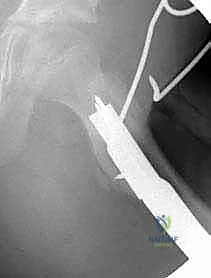

3. إدخال سلك الدليل (Guide Wire Placement)

هذه هي الخطوة الأكثر أهمية. باستخدام الأشعة المباشرة، يقوم الدكتور بإدخال سلك معدني رفيع في عنق عظم الفخذ باتجاه الرأس. يتم وضع هذا السلك بزاوية محسوبة مسبقاً بدقة متناهية لتتطابق مع زاوية الشريحة (90 درجة).

4. تحضير مسار الشريحة النصلية (Seating Chisel)

باستخدام أداة خاصة تشبه الإزميل، يتم حفر مسار دقيق داخل العظم الإسفنجي لعنق الفخذ، وذلك تمهيداً لإدخال نصل الشريحة المعدنية.

5. قطع العظم (The Osteotomy)

باستخدام منشار جراحي عالي الدقة، يقوم الدكتور هطيف بقطع عظم الفخذ أسفل منطقة المدور الكبير (Subtrochanteric). في هذه المرحلة، يتم إزالة إسفين عظمي صغير (Wedge) بالزاوية المطلوبة لتصحيح التشوه.

6. إدخال الشريحة والتثبيت (Plate Insertion & Fixation)

يتم إدخال نصل الشريحة ذات الزاوية 90 درجة في المسار الذي تم تحضيره في عنق الفخذ. ثم يتم ضم جزئي العظم المقطوعين معاً (إغلاق الفجوة)، مما يؤدي فوراً إلى تغيير زاوية عنق الفخذ إلى الوضع الطبيعي الجديد. يتم تثبيت الجزء الطويل من الشريحة على جسم عظم الفخذ باستخدام براغي قوية من التيتانيوم أو الفولاذ الطبي المقاوم للصدأ.

لماذا الشريحة ذات الزاوية 90 درجة (90-Degree Blade Plate) تحديداً؟

قد يتساءل البعض: لماذا يصر الأستاذ الدكتور محمد هطيف على استخدام هذا النوع المحدد من الشرائح في عمليات قطع عظم الفخذ الداني التقويمي؟ الإجابة تكمن في الميكانيكا الهندسية:

- التثبيت فائق الصلابة (Rigid Fixation): النصل العريض للشريحة الذي يدخل في عنق الفخذ يوفر ثباتاً دورانياً وزاوياً لا مثيل له، مما يمنع العظمة من التحرك أثناء فترة الالتئام.

- التحكم الدقيق في الزوايا ثلاثية الأبعاد: تسمح هذه الشريحة بتصحيح زاوية الميل (Varus)، وكذلك تصحيح الدوران الخاطئ للعظمة (Derotation) في نفس الوقت.